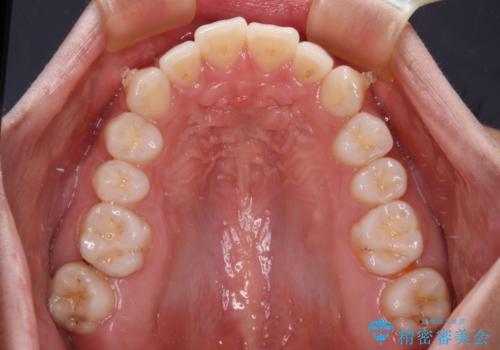

【モニター】突出した前歯 補助装置を併用したインビザライン矯正

- 上下前歯が非接触となり、前方に突出していることを気にして来院された患者様です。

咬合力が強く、全体的に歯がすり減っているため、インビザライン単独での上顎歯列移動は困難と判断し、補助装置により上顎歯列を後方移動させ、その後インビザラインにて仕上げていくこととしました。

補助装置なしでも改善できる可能性はありましたが、補助装置で確実性を上げ、短期間できっちりと仕上げることができました。